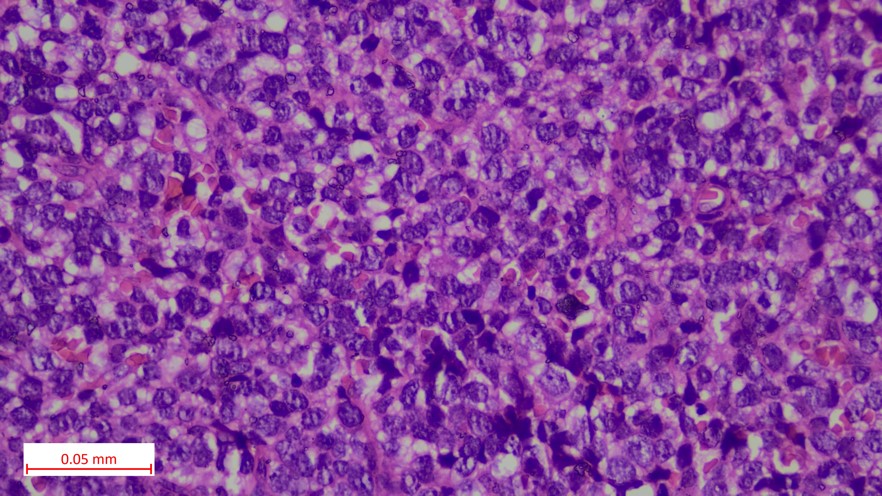

Histopathological findings

• Tumor cells showed a round to oval nucleus with inconspicuous nucleoli, scant eosinophilic to clear cytoplasm (PAS positive) and indistinct cytoplasmic borders. In few areas, tumor cells showed hyperchromatic angulated nuclei

Immunohistochemical findings

• Tumor cells showed diffuse membranous immunopositivity for CD99